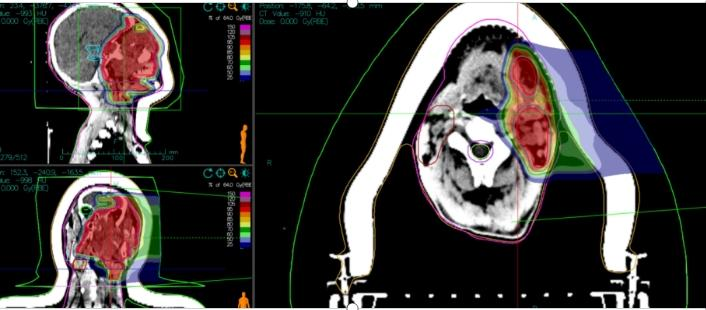

1. **Target Delineation:**

- GTV: MRI-indicated irregular nodules and masses in the left nasal cavity, nasopharynx, oropharynx, left maxillofacial region, periorbital area, and nasal root, including surrounding invaded tissues. A 0.5 cm margin was added to form PTVboost.

- CTV: High-risk areas based on GTV, with appropriate cropping in the right eye and right optic nerve. A 0.3 cm margin was added to form PTV1.

- GTVnd_R: Enlarged lymph nodes in the right neck level II.

- GTVnd_L: Enlarged lymph nodes in the left neck levels Ib and II.

- CTVnd_R: Lymph node drainage area in the right neck level II.

- CTVnd_L: Lymph node drainage area in the left neck levels Ib-II.

A 0.3 cm margin was added to form PTVnd_R and PTVnd_L.

2. **Prescription Dose:**

- PTVboost: 8 Gy(RBE)/2 fractions

- PTV1, PTVnd_R, PTVnd_L: 64 Gy(RBE)/16 fractions

- Total dose to the tumor area: 72 Gy(RBE)/18 fractions

Figure 1: The total dose to the tumor region reached 72 Gy (RBE).

Figure 2: PTVnd_L 64 Gy (RBE)/16 fx.

Figure 3: PTVnd_R 64 Gy (RBE)/16 fx, with the total dose to the tumor region reaching 72 Gy (RBE).